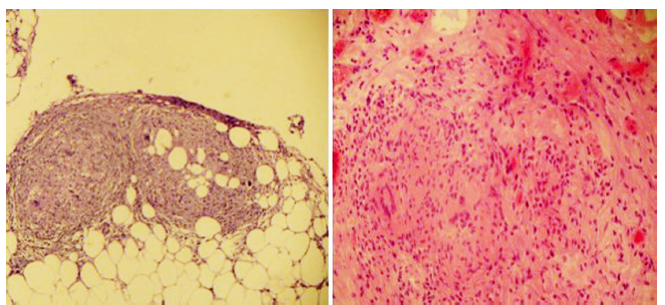

El citoquímico del líquido ascítico mostró un gradiente de albúmina suero-líquido (GASA) de 0,6 compatible con ascitis no hipertensiva; leucocitos de 2400/mm3, 100 % linfocitos, con glucosa en 82,4 mg/dL y coloración de Gram negativa para gérmenes. Se amplió el estudio con niveles de adenosina-desaminasa (ADA) en el líquido peritoneal con un valor de 102 U/L (referencia < 36 U/L) y el citológico mostró linfocitosis y fue negativo para malignidad. Se realizó una tomografía axial computarizada (TAC) de tórax y abdomen con el fin de descartar una neoplasia como diagnóstico diferencial. La TAC de abdomen mostró cambios en la densidad del peritoneo con engrosamiento, múltiples nódulos pequeños en el tercio superior del abdomen que realzaban con el medio de contraste (Figura 1), hígado pequeño y ascitis abundante; y la TAC de tórax mostró escaso derrame pleural bilateral. Se definió realizar una laparoscopia para la toma de biopsias en la que se evidenció un compromiso extenso de todo el peritoneo por micronódulos amarillentos, algunas adherencias interasas, abundante líquido verdoso no purulento en la cavidad, así como hígado de aspecto cirrótico con algunos micronódulos; se tomó biopsia de peritoneo e hígado. El estudio histológico del peritoneo fue compatible con inflamación granulomatosa, con tinción de Ziehl-Neelsen (ZN) negativa (Figura 2), pero con reacción en cadena de la polimerasa (PCR) positiva para Mycobacterium tuberculosis. El enzimoinmunoanálisis de adsorción (ELISA) para VIH fue negativo.

Figura 2 Estudio histopatológico. Coloración de hematoxilina-eosina con evidencia de inflamación crónica granulomatosa sugestiva de TB. Coloración ZN negativa para bacilo resistente a ácido-alcohol.